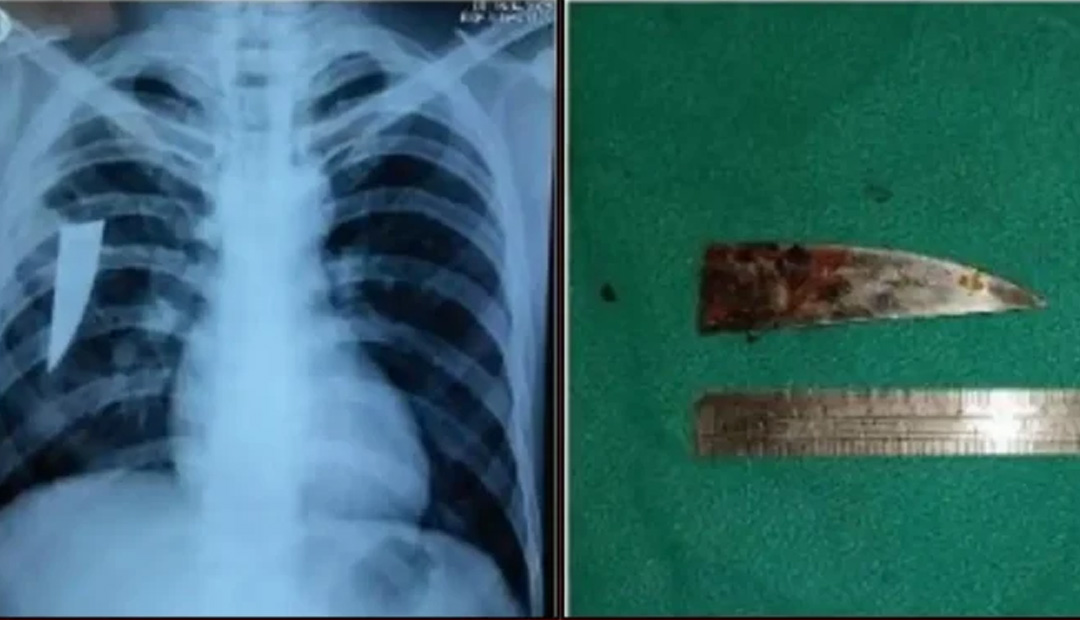

ବ୍ରହ୍ମପୁର: ଏମ୍କେସିଜି ମେଡିକାଲ କଲେଜ ଓ ହସପିଟାଲର ଡାକ୍ତରମାନେ ଏକ ବିରଳ ଅପରେସନ କରିବାରେ ସଫଳ ହୋଇଛନ୍ତି। ୩ ବର୍ଷ ଧରି ଜଣେ ଯୁବକଙ୍କ ଛାତି ଭିତରେ ଥିବା ୮ ସେମି ଲମ୍ବର ଏକ ଛୁରିକୁ ଅେସ୍ତ୍ରାପଚାର କରି ଡାକ୍ତର ବାହାର କରିଛନ୍ତି। ଛୁରିଟି ସଂପୃକ୍ତ ଯୁବକଙ୍କ ବାମ ପଟ ବେକ ତଳେ ପଶିଥିବା ବେଳେ ତାହାକୁ ଡାକ୍ତରମାନେ ଡାହାଣ ପାର୍ଶ୍ବ ଫୁସଫୁସ ଭିତରେ ଠାବ କରିଥିଲେ। ସିଟିଭିଏସ ବିଭାଗ (ହୃଦ୍ବକ୍ଷ ଶଲ୍ୟ ଚିକିତ୍ସା ବିଭାଗ)ର ମୁଖ୍ୟ ଆସୋସିଏଟ ପ୍ରଫେସର ଡା. ସାରଦା ପ୍ରସନ୍ନ ସାହୁଙ୍କ ନେତୃତ୍ବରେ ଗଠିତ ଡାକ୍ତରୀ ଟିମରେ ଆନେସ୍ଥେସିଆ ବିଭାଗ ଆସୋସିଏଟ ପ୍ରଫେସର ଡା.ସଞ୍ଜୀବ ପାତ୍ର, ଡା. ବାରୟନ ସ୍ବାଇଁ ଓ ଡା. ପ୍ରଦୀପ୍ତ କୁମାର ସାହୁ, ନର୍ସିଂ ଅଫିସର ସୁଭଦର୍ଶନୀ ଓ ମନସ୍ବିନୀ ପ୍ରମୁଖ ଅେସ୍ତ୍ରାପଚାରରେ ସାମିଲ ଥିଲେ। ଅେସ୍ତ୍ରାପଚାର ପରେ ଯୁବକଙ୍କ ସ୍ବାସ୍ଥ୍ୟବସ୍ଥା ସ୍ଥିର ରହିଛି ା ତାଙ୍କୁ ସିଟିଭିଏସ ବିଭାଗ ଆଇସିୟୁରେ ରଖି ଚିକିତ୍ସା କରାଯାଉଛି।

ଆଜକୁ ୯ ମାସ ତଳେ ଯୁବକଙ୍କ କଫରେ ରକ୍ତ ପଡିବା ପରେ ସେ ଡାକ୍ତରଖାନା ଯାଇ ଦେଖାଇଥିଲେ। କଫ ପରୀକ୍ଷାରୁ ତାଙ୍କୁ ଯକ୍ଷ୍ମା ଥିବା ଜଣାପଡିଥିଲା। ସେ ଯକ୍ଷ୍ମା ଭଲ ହେବା ପାଇଁ ଔଷଧ ଖାଇଥିଲେ। ହେଲେ ସେତେବେଳେ ମଧ୍ୟ ଛୁରିଟି ଛାତି ଭିତରେ ଅଛି ବୋଲି ଜଣାପଡିନଥିଲା। କିଛି ଦିନ ତଳେ ଛାତିରେ ଯନ୍ତ୍ରଣା ହେବାରୁ ଯୁବକ ଜଣଙ୍କ ୧୯ ତାରିଖରେ ଏମ୍କେସିଜିକୁ ଯାଇଥିଲେ। ସେଠାରେ ଡାକ୍ତରଙ୍କ ପରାମର୍ଶକ୍ରମେ ଛାତିର ଏକ୍ସ-ରେ ବାହାର କରାଯାଇଥିଲା। ‘ଏକ୍ସ-ରେ’ କରାଯିବା ପରେ ତାଙ୍କ ଡାହାଣପଟ ଛାତିରେ ଏକ ଛୁରିର ଖଣ୍ଡ ରହିଥିବା ଡାକ୍ତରମାନେ ଜାଣିବାକୁ ପାଇଥିଲେ। ସିଟିସ୍କାନ ଓ ବ୍ରୋଙ୍କୋସ୍କୋପି କରାଯିବା ପରେ ଫୁସଫୁସ ଭିତରେ ଏହି ଛୁରି ରହିଥିବା ଜଣାପଡିଥିଲା। ଏହାପରେ ଯୁବକଙ୍କ ଛାତି ଚିରି ଛୁରି ବାହାର କରିବାକୁ ସିଟିଭିଏସ ବିଭାଗର ଡାକ୍ତରମାନେ ପଦକ୍ଷେପ ନେଇଥିଲେ। ଗତକାଲି ଏହି ଅପରେସନ ଶେଷ ହୋଇଛି। ଅେସ୍ତ୍ରାପଚାର କରିବାକୁ ୩ ଘଣ୍ଟାରୁ ଅଧିକ ସମୟ ଲାଗିଥିବା ବିଭାଗୀୟ ମୁଖ୍ୟ ପ୍ରଫେସର ସାହୁ କହିଛନ୍ତି।